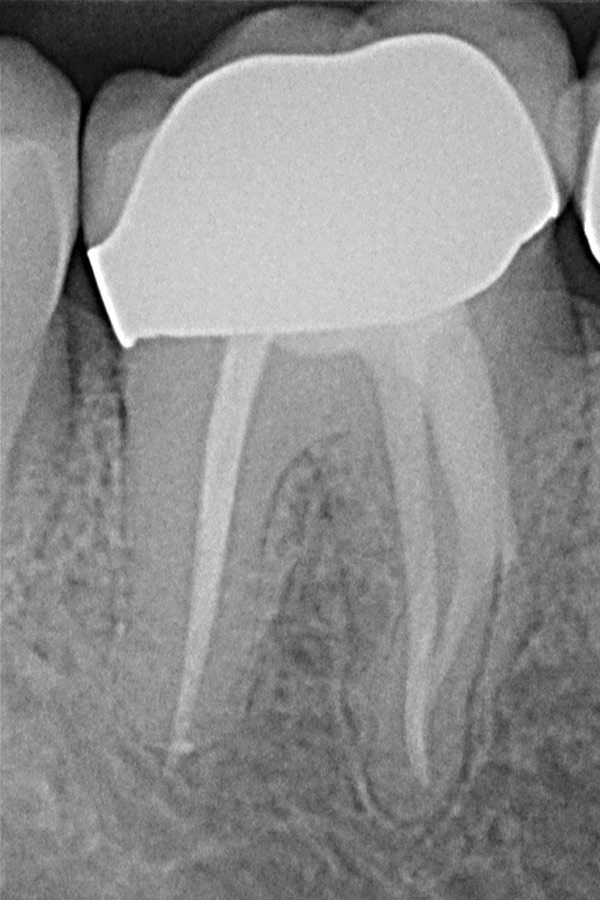

Unterkiefer-Molar mit unvollständiger Wurzelfüllung und Zahnwurzelentzündung

Ausgeheilte Entzündung 1 Jahr später nach Revisionsbehandlung